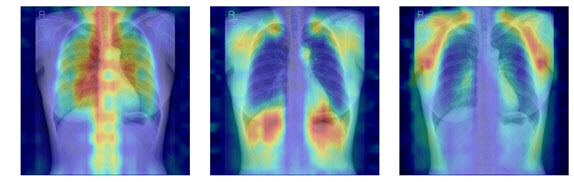

흉부X선에서 파운데이션 모델이 골다공증 판독을 위해 주목한 영역을 시각화한 이미지.

연구팀은 여기에 더해 AI가 실제로 어떤 뼈를 근거로 삼아 판단하는지까지 확인할 수 있도록 ‘설명 가능성’ 평가 체계를 설계했다. 뼈를 모두 가린 상태에서 특정 뼈 부위를 추가해 성능이 얼마나 향상하는지 확인하는 ‘차단 분석 방식(Δbone)’과 Grad-CAM으로 나타난 AI의 주목 영역이 실제 뼈 위치와 얼마나 일치하는지를 계산하는 ‘유의성 지도 방식(IoUbone)’을 통해, AI가 임상적으로 중요한 뼈 구조를 근거로 판단하는지를 정량적으로 검증했다.